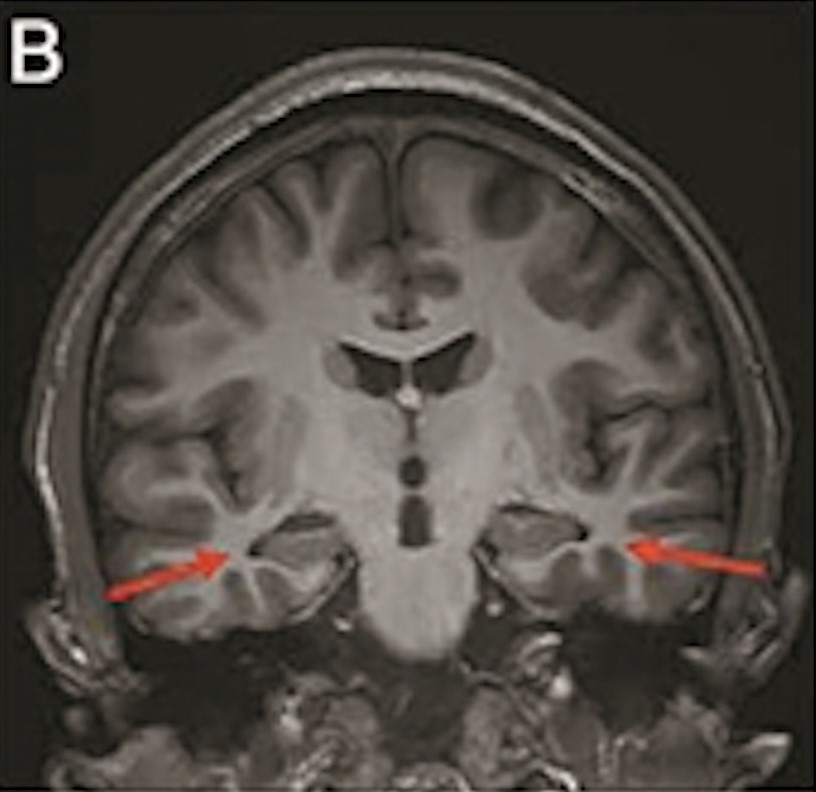

最年輕的19歲阿茲海默癥男子腦部掃描結(jié)果:

▲19歲阿茲海默癥(認知障礙癥/腦退化癥)男子腦部掃描結(jié)果。北京青年報

該名19歲男子到醫(yī)院接受多項檢查,包括腦脊液指標檢測及正電子掃描。結(jié)果顯示,他出現(xiàn)輕度腦萎縮等癥狀,最終被臨床診斷為“阿茲海默癥”。